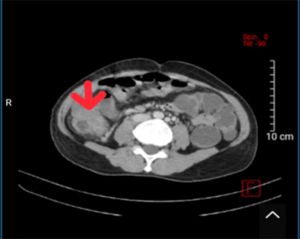

CASE LÂM SÀNG: ĐIỀU TRỊ MIỄN DỊCH BỆNH NHÂN UNG THƯ HẮC TỐ DI CĂN HẠCH, PHỔI TẠI TRUNG TÂM Y HỌC HẠT NHÂN VÀ UNG BƯỚU, BỆNH VIỆN BẠCH MAI.

CASE LÂM SÀNG: ĐIỀU TRỊ MIỄN DỊCH BỆNH NHÂN UNG THƯ HẮC TỐ DI CĂN HẠCH, PHỔI TẠI TRUNG TÂM Y HỌC HẠT NHÂN VÀ UNG BƯỚU, BỆNH VIỆN BẠCH MAI. GS.TS Mai Trọng Khoa, BSNT. Mai Thị Quỳnh, PGS.TS Phạm Cẩm Phương, TS. Phạm Văn Thái, TS. Nguyễn Thanh...